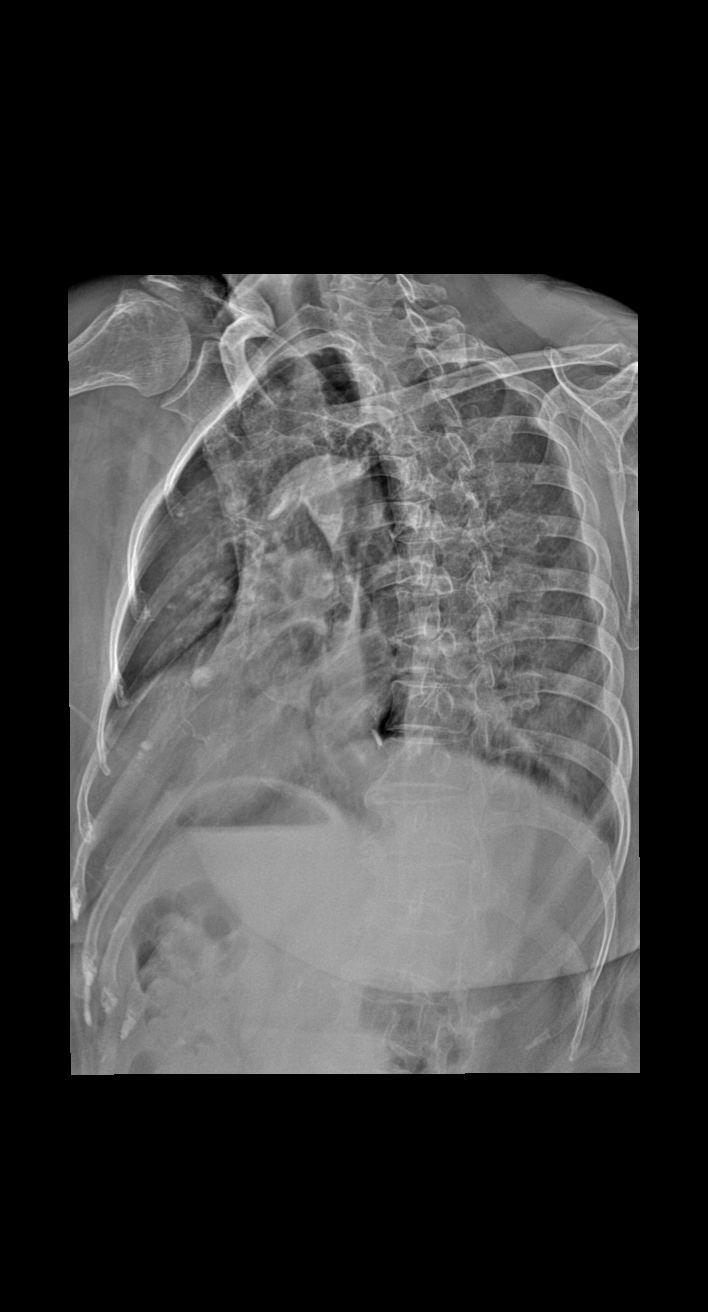

女74骨折一月复查